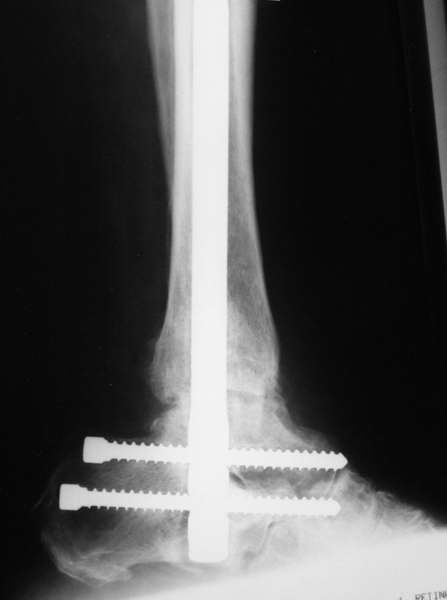

Можно: 65-летняя пациентка, оперирована по поводу несросшегося в гипсе перелома лодыжек с патологической вальгусной установкой стопы и выраженным нарушением опрной функции. Оперирована через 6 месяцев после травмы. Рентгенограммы через 4 месяца после операции.

Существуют специальные системы для артродеза голеностопного сустава. См. приложение